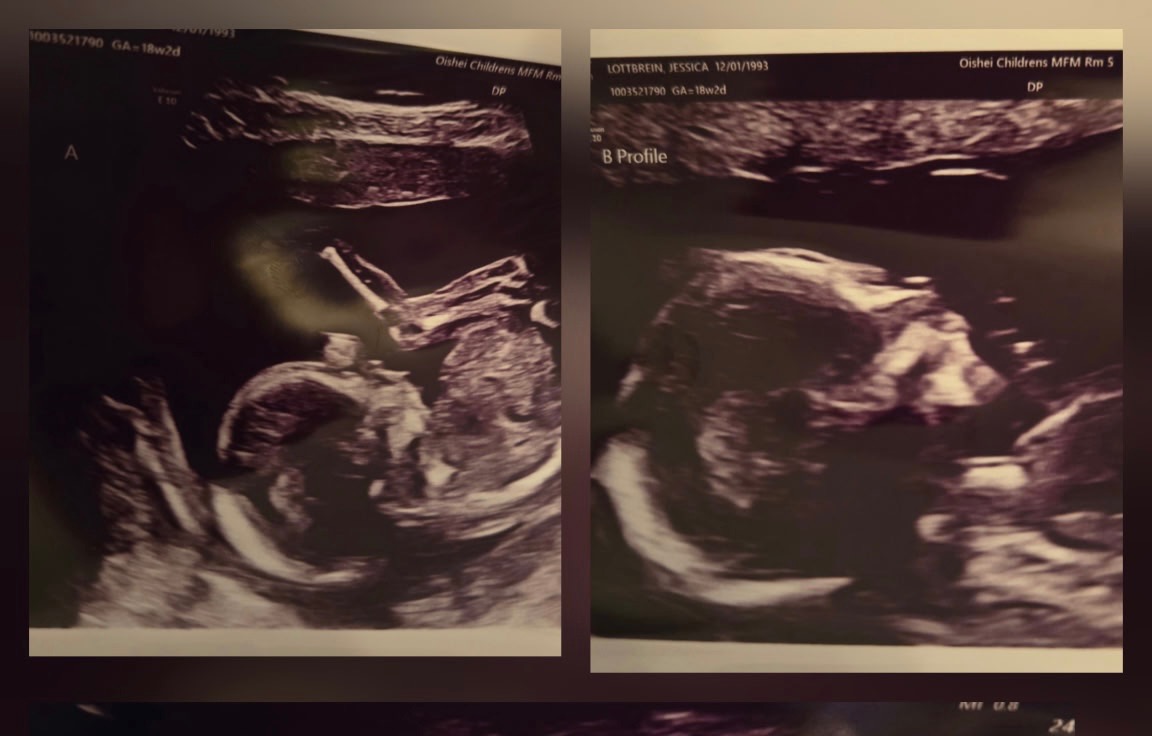

Jess is an amazing mother to her two young daughters, Hannah and Brooke, and a dedicated wife to the love of her life, John. They recently decided to expand their family and went through some fertility treatments. It was not IVF. She spontaneously released five eggs and all five were fertilized. Once again, this was not an intentional thing, nor is it something that could’ve been predicted. So now she is almost 20 weeks pregnant with quintuplets! For those of you who don’t know, that is five babies tucked safely away in her belly. The babies are thriving; they’re growing at appropriate rates, and as of right now, there’s no sign of major complications.